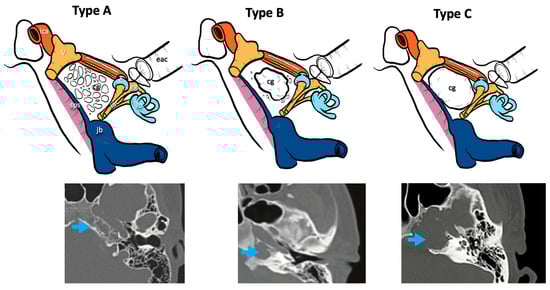

Three radiological types of cholesterol granuloma were distinguished according to the different radiological features of the petrous apex bone modifications and remodeling caused by this lesion (Figure 1):

Figure 1.

CT classification of cholesterol granulomas. V, fifth cranial nerve; ica, internal carotid artery; jb, jugular bulb; iac, internal auditory canal; lb, labyrinthine block; c, cochlea; eac, external auditory canal; gg, geniculate ganglion; sps, superior petrosal sinus; cg: cholesterol granuloma; blue arrows, cholesterol granuloma on the CT scans.

- Type A cholesterol granuloma: presence of a cholesterol granuloma of the petrous apex with preserved cellularity in the absence of erosive phenomena and/or of cellular confluence.

- Type B cholesterol granuloma: presence of a cholesterol granuloma of the petrous apex with erosive phenomena and cellular confluence without any involvement of the bony limitations that cover the noble structures of the apex (otic capsule, IAC, middle and posterior cranial fossa dura, ICA, jugular bulb).

- Type C cholesterol granuloma: presence of a cholesterol granuloma of the petrous apex with erosive and cellular confluence phenomena with involvement of the bony limitations covering the noble structures of the apex (otic capsule, IAC, dura of the middle and posterior cranial fossa, ICA, jugular bulb).